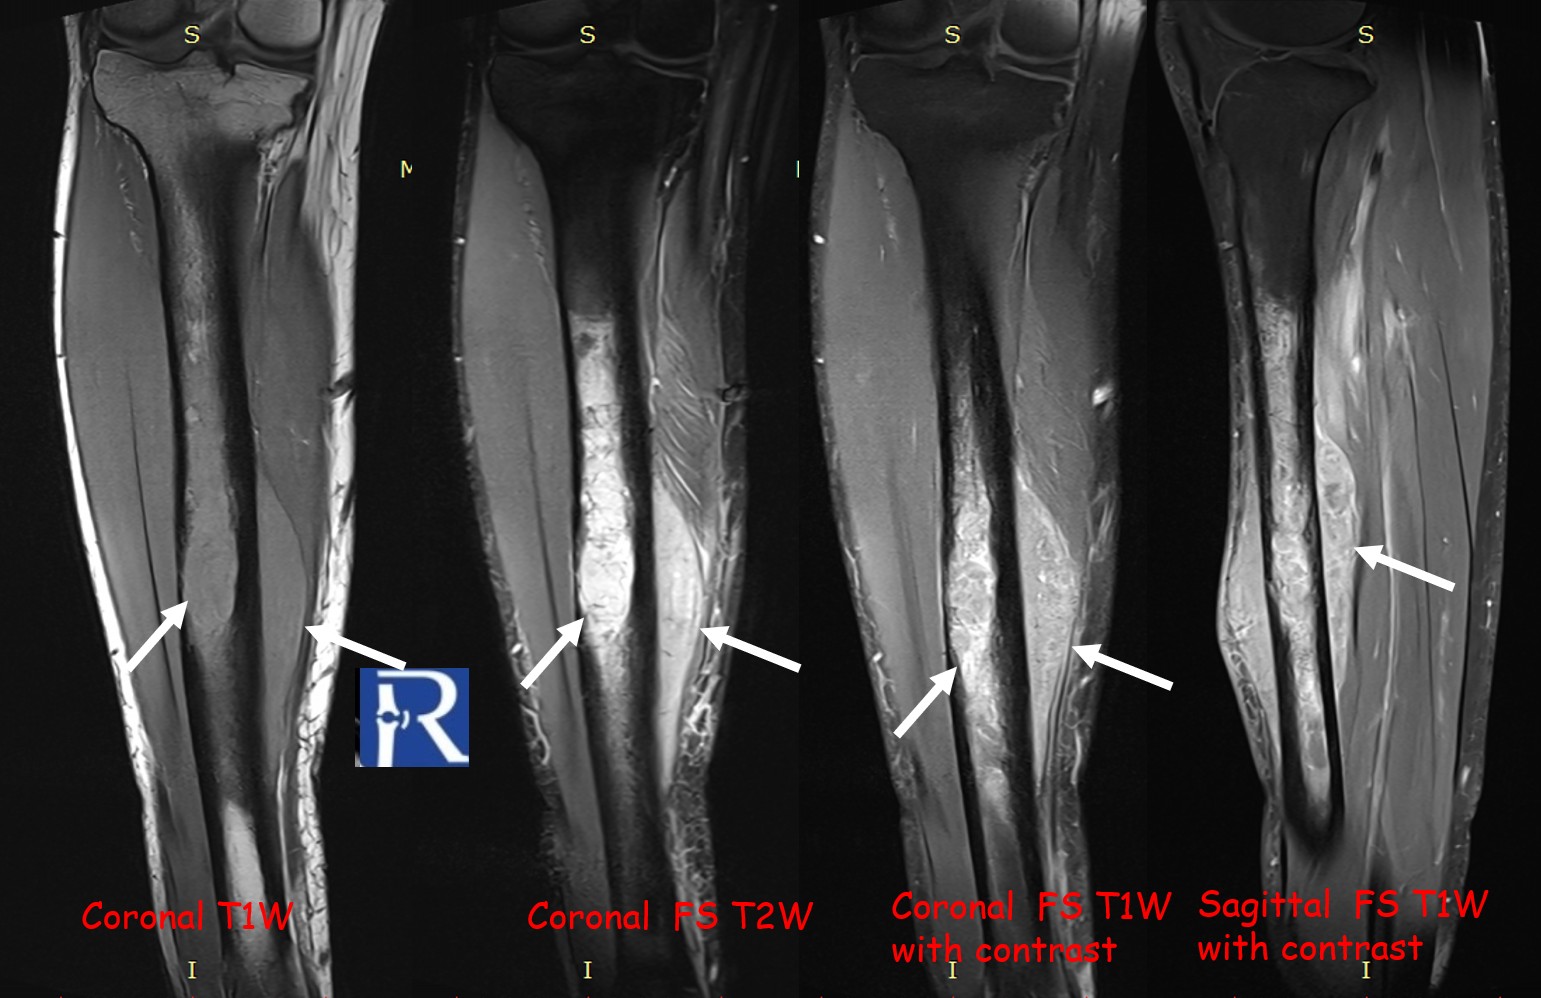

MRI revealed a significant soft-tissue component extending beyond the cortical margin, appearing hypointense on T1-weighted and intermediate on T2-weighted sequences, with heterogeneous contrast enhancement.

Diffusion-weighted imaging (DWI) showed marked diffusion restriction in both osseous and soft-tissue components, reflecting high cellularity.

The lesion exhibited limited cortical destruction, yet extensive soft-tissue extension. Multiple conglomerate inguinal and pelvic lymph node enlargements were also identified, demonstrating signal characteristics similar to those of the primary lesion.

These imaging findings—particularly the absence of periosteal reaction, intermediate T2 signal, and marked DWI restriction—favored the diagnosis of lymphoma over Ewing sarcoma.

However, certain imaging clues may guide the differential diagnosis. Lymphoma typically demonstrates limited cortical destruction, absence of periosteal reaction, and intermediate T2 signal intensity, whereas Ewing sarcoma tends to produce more prominent periosteal layering and higher T2 hyperintensity. Diffusion-weighted imaging is a powerful adjunct, with strong restriction patterns highly suggestive of lymphoma due to its dense cellular structure.